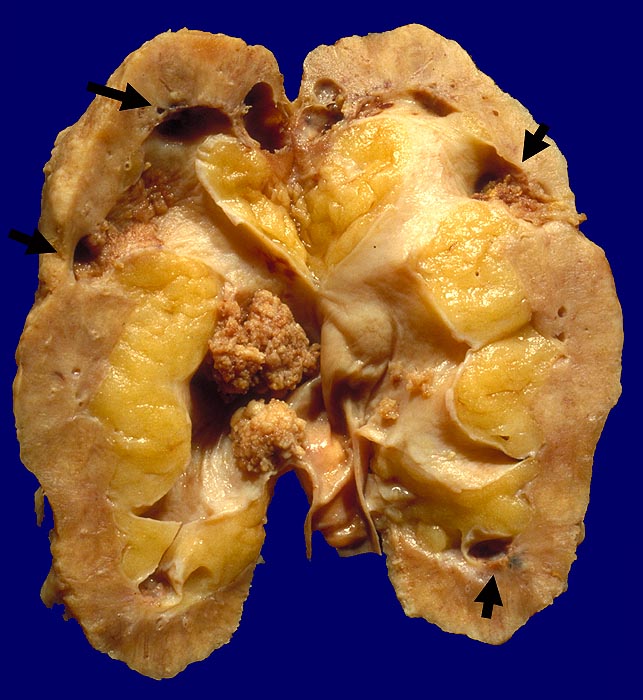

Morphologie:

Pathomorphologisch unterscheiden sich Urothelkarzinome bei Phenacetinabusus nicht von sporadischen Urothelkarzinomen abgesehen von ihrer bevorzugten Lokalisation im Nierenbecken und der allenfalls ausserhalb des Tumors in der Harnwegsschleimhaut nachweisbaren Kapillarosklerose.

Morphologische Merkmale:

• Solider Tumor mit fokalen Entzündungsinfiltraten.

• Polymorphe Tumorzellen mit unscharfen Zellgrenzen und bläschenförmigen (=vesikulären) Kernen.

• Zahlreiche Mitosen.

• Ureter mit verdickten Kapillaren (Kapillarosklerose).